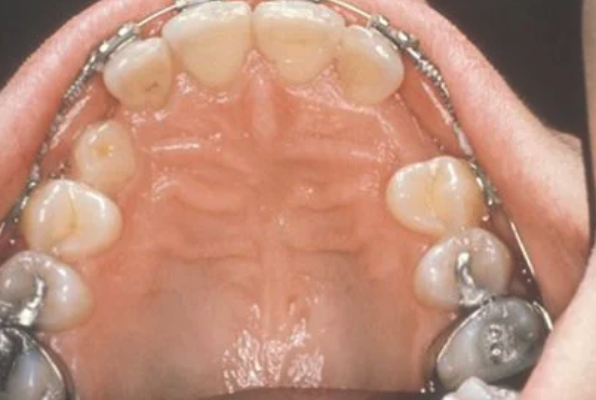

Normally, the maxillary cuspid teeth are the last of the “front” teeth to erupt into place. They usually come into place around age 13 and cause any space left between the upper front teeth to close tighter together. If a cuspid tooth gets impacted, every effort is made to get it to erupt into its proper position. The techniques involved to aid eruption can be applied to any impacted tooth in the upper or lower jaw, but most commonly they are applied to the maxillary cuspid (upper eye) teeth. Sixty percent of these impacted eyeteeth are located on the palatal (roof of the mouth) side of the dental arch. The remaining impacted eye teeth are found in the middle of the supporting bone, but are stuck in an elevated position above the roots of the adjacent teeth, or are out to the facial side of the dental arch.